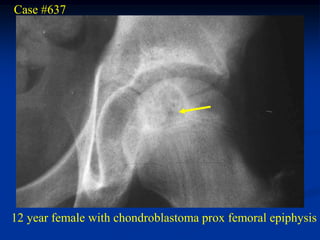

Case #637

12 year female with chondroblastoma prox femoral epiphysis

CT scan

Another CT cut